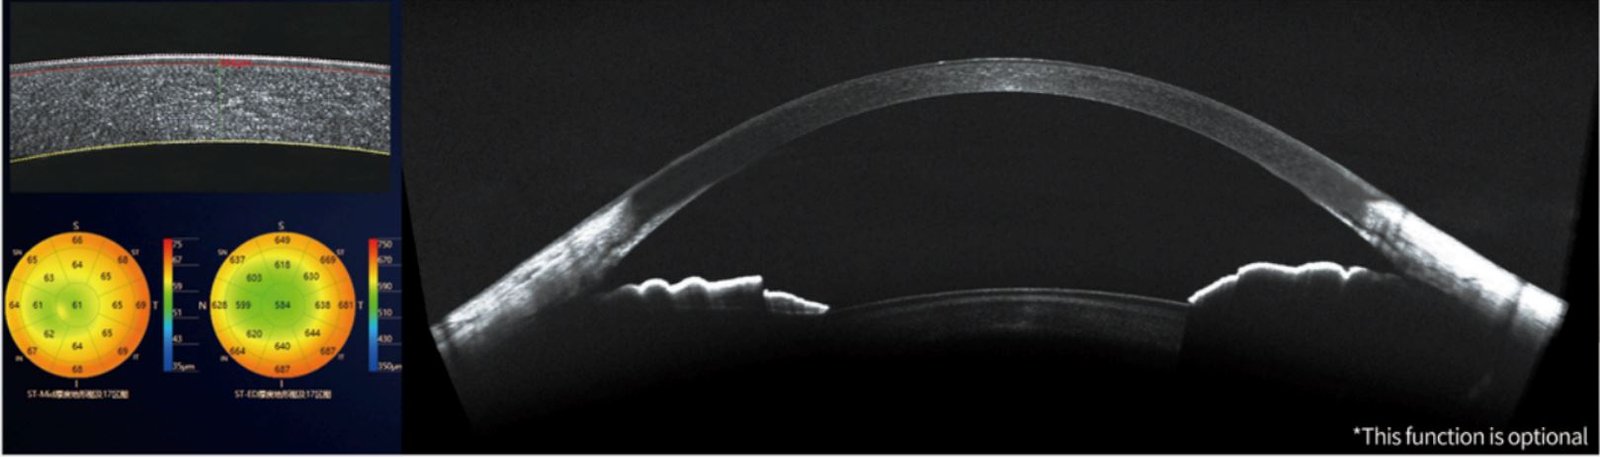

Anterior segment detection - Accurate measurement

Panoramic anterior segment analysis | Panoramic anterior segment presentation • Corneal thickness map presentation Corneal dividing line Thickness measurement presentation